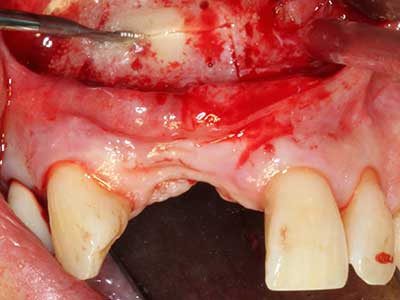

Aplicación: Partición ósea / Cortical Split

El tejido óseo no solo tiene un contenido puramente mineral, sino que también presenta una importante proporción de fibras de colágeno. Esto no solo garantiza una buena resistencia a la presión, sino también una cierta flexibilidad, que puede aprovecharse para la realización de aumentos. En la plastia de expansión clásica a efectos de una partición ósea, la cresta maxilar atrofiada se divide en su eje longitudinal y, tras alcanzar una profundidad de osteotomía suficiente, se extiende con cuidado (fig. 13-16), en un caso ideal sin desperiostizar de forma visible el maxilar (Brugnami, Caiazzo et al. 2014, Stricker, Fleiner et al. 2014). Los sistemas de tornillos y placas con distancia de expansión creciente han demostrado su eficacia para distanciar entre sí las dos tablas óseas por debajo del umbral de rotura. Por regla general, se requieren anchuras de hueso residual de al menos 3 a 4 mm (Chiapasco, Zaniboni et al. 2006) para garantizar una flexibilidad y una cobertura ósea suficientes de los implantes que van a incorporarse. En caso necesario, una osteotomía de descarga vertical unilateral o bilateral puede mejorar la flexibilidad. Como alternativa a la técnica clásica se ha descrito una combinación con otras técnicas de aumento, sobre todo en la parte bucal.

Con el uso de sierras piezoeléctricas la división se efectúa de forma especialmente cuidadosa y sin pérdidas importantes de las dimensiones, por lo que no se han encontrado diferencias significativas entre los implantes realizados en el maxilar dividido y en la cresta alveolar no deficitaria (Chiapasco, Zaniboni et al. 2006, Danza, Guidi et al. 2009). No obstante, precisamente en la partición profunda y limitada de forma local, es preciso asegurarse de que exista una adecuada irrigación por agua para evitar que se produzcan sobrecargas térmicas en las áreas de osteotomía apical.

Fig. 13: En este paciente de 52 años con una anchura del hueso residual del maxilar inferior de 4 mm, hay que asegurarse de que exista refrigeración por agua adecuada durante la partición del hueso.

Fig. 14: Incorporación de cuatro implantes RSX cónicos (Bego Implant Systems, Bremen).